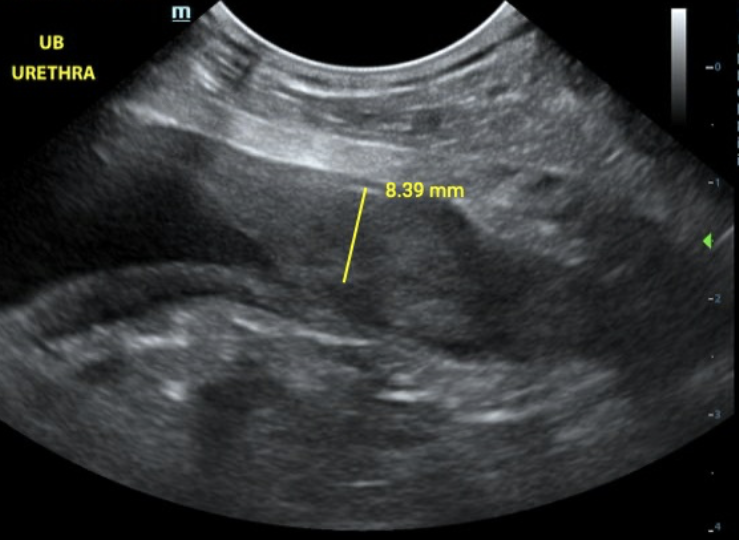

Canine urethra visualized on ultrasound

The Importance of Urethral Imaging in Bladder Ultrasound: A Case Study and Practical Techniques

When performing bladder ultrasounds, it's easy to focus primarily on sagittal and transverse views. However, the urethra is a critical area where...